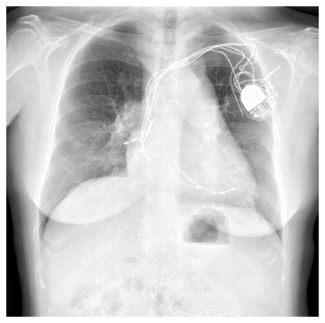

Bilateral femoral arterial access was obtained using 8 Fr 45 cm long sheaths. The RCA was initially engaged with an 8 Fr JR4 guide that provided poor to moderate support. The left main was engaged with a XB 3.5 guide. Coronary angiography using dual injection demonstrated marked calcification in the RCA with a 30 mm mid level occlusion (Figure 1A). The mid RCA filled via collaterals from the LAD and the circumflex and reconstitution of the mid RCA occurred at the site of origin of a large acute marginal branch.

We attempted to wire retrogradely, but were unable to cross through septal collaterals in part due to a previously placed LAD stent. We engaged the RCA with a 7 Fr Champ 2 guide and wired into the acute marginal distal to the CTO using a Pilot 150 wire (Abbott Vascular) through a Finecross microcatheter (Terumo) (Figure 1B). We encountered severe difficulty crossing the CTO with a balloon. We inflated several 1.5 mm balloons into the lesion but were unsuccessful in crossing. We used a 7 Fr Guideliner catheter (Vascular Solutions) to deeply engage the RCA and were then able to cross with a 1.5 mm balloon. We predilated several times with 1.5 mm and 2.0 mm balloons, restoring antegrade flow through the RCA CTO (Figure 1C).

We could not wire antegradely into the mid RCA in spite of using multiple wires, as there was an acute bend at the origin of the acute marginal branch. We eventually used a "hairpin wire" technique, in which a Whisper wire (Abbott Vascular) was bent approximately 3 cm from its tip, advanced into the acute marginal branch, and pulled back (Figures 1D and 1E). We then attempted to advance a balloon into the distal RCA, but were not successful and in the process, the guidewire and guide catheter position were lost.

We engaged the RCA again with an 8 Fr JR4 guide and rewired into the acute marginal branch distal to the CTO and into the distal RCA using the same "hairpin wire" technique. We once again encountered significant difficulty delivering equipment to the distal RCA. Several 1.5 mm balloons could not cross. We were finally able to advance a Corsair catheter (Asahi Intecc) (arrow, Figure 2B) to the distal RCA using an anchor balloon technique with a 2.5 mm balloon into a small proximal RCA conus branch (arrowhead, Figure 2B). The Whisper wire (Abbott Vascular) was exchanged for an Ironman wire (Abbott Vascular, arrowhead, Figure 2C), which enabled sequential delivery of 2.0, 2.5, and 3.0 mm balloons and predilation of the entire proximal, mid, and distal RCA. We were then able to deliver three 3.0 mm x 28 mm Xience V everolimus-eluting stents (Abbott Vascular) using a Guideliner catheter (Vascular Solutions, arrow, Figure 2C) for extra guide support. The stents were postdilated with a 3.5 mm non-compliant balloon, providing an excellent final angiographic result (Figure 2D), as confirmed by intravascular ultrasonography. The total fluoroscopy time and air kerma radiation dose were 39.2 minutes and 7.4 Gray, respectively, and 358 mL of contrast were administered. At 1-month follow-up the patient was angina-free and had significantly increased his daily activities.